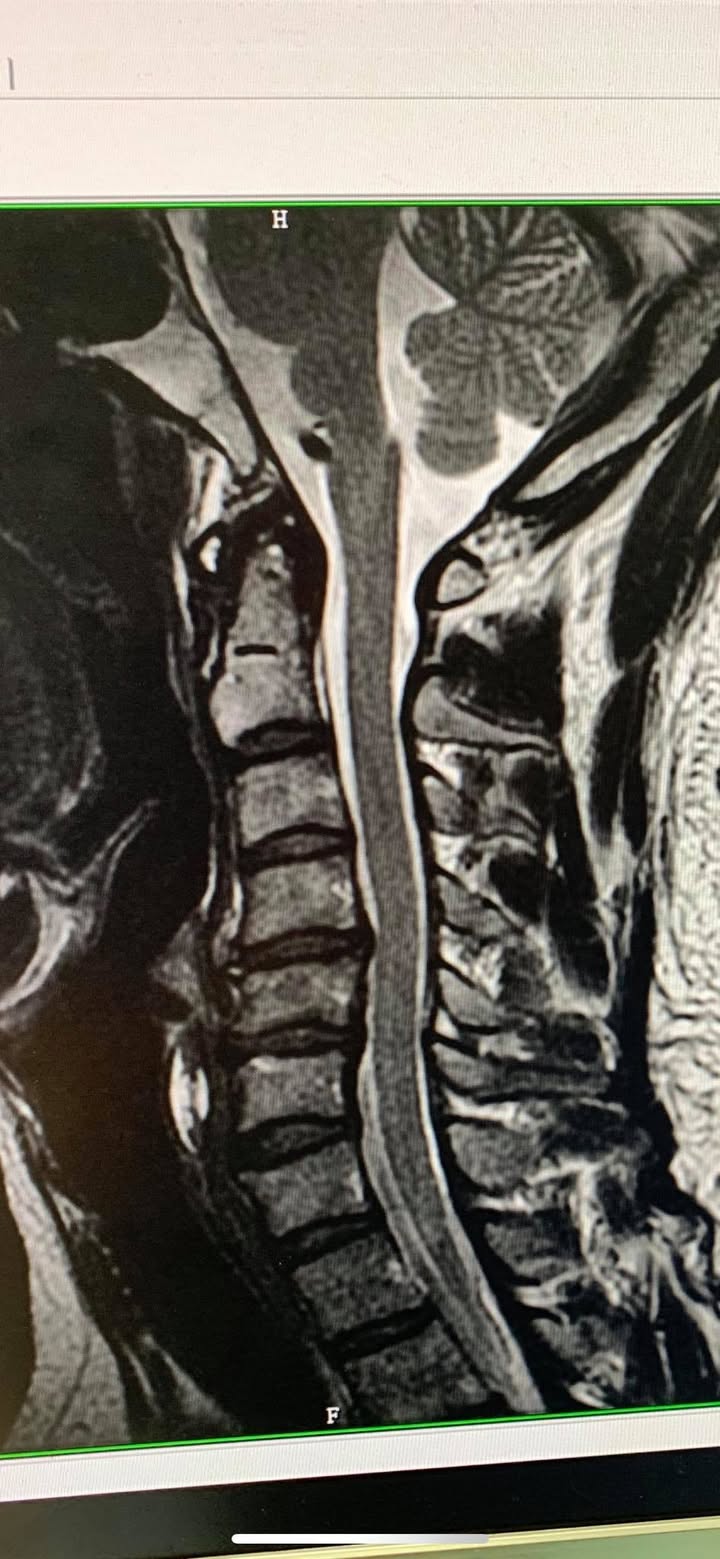

Cervical Spine Treatment Cases 頸椎治療案例 感謝新竹市羅小姐熱情見證 頸椎整合中醫微創療法逆轉勝 2020.03.18 感謝台北市👮♀️陳大哥熱情見證 困擾三年頸椎疼痛逆轉勝 騎機車手麻到無法煞車劇痛不... 2020.03.13 感謝台中市許大姐熱情見證 頸椎壓迫導致右臂酸麻痛五個月 脊椎整合中醫微創逆轉勝 2020.03.12 史上第一次碰到全聾啞人士聘用手語翻譯人員來診所接受脊椎整合中醫維創! 2020.02.22 #嚴重的頸椎反弓醫案 #疼痛超過半年左側肩膀麻痛連手臂 #感謝葉先生熱情見證 2020.02.22 #頸椎痛到無法睡覺怎麼回事 #神經根型頸椎病醫案 #感謝台北吳小姐熱情見證 #脊椎整合... 2020.02.13 #頸椎間盤突出痛到右手完全沒力 #神經根型頸椎病合併輕微脊髓壓迫 #原本考慮裝設人工... 2020.02.07 #脊髓型嚴重壓迫患者 #可能非針刀類型患者 2020.01.23 #頸椎壓迫醫案見證 #脊椎整合中醫微創療法原理說明 #感謝新竹余先生熱情見證 #什麼症... 2020.01.22 #頸椎壓迫神經根醫案 #疼痛超過三年以上 #來診前幾個月大痛到無法睡覺 #感謝新莊陳大... 2020.01.10 #感謝台大學長熱情見證頸椎針刀療法 #脊椎整合中醫微創療法 2019.12.17 #感謝宜蘭李大哥熱情見證 #神經根型頸椎病痛到上臂肩膀麻痛 #原本想說熱愛的衝浪可能... 2019.12.08 😂原本都準備要去開刀了! 😢醫學中心報價兩節椎間盤報價52萬 😄感謝苗栗患者熱情見證... 2019.11.22 ❇️頸椎間盤突出痛到完全無法洗頭 #核磁共振證實C4C5突出壓迫 #上樓梯頭往後面抬就誘發... 2019.11.13 #頸椎痛到無法睡覺怎麼回事 #原本認真考慮開刀治療 #感謝雲林患者熱情北上見證 #脊椎... 2019.10.21 ← 上一頁 6 7 8 9 10 下一頁 →